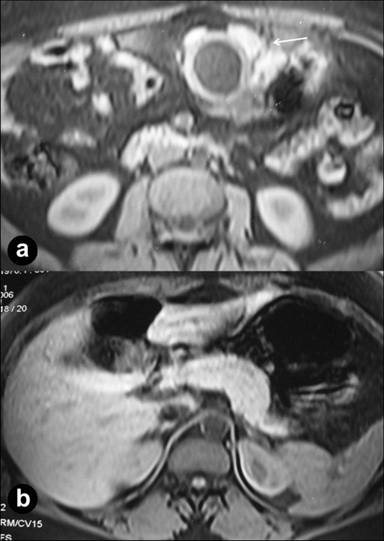

Magnetic resonance imaging of the abdomen showed a hypointense lesion with surrounding soft tissue of intensity similar to that of the pancreas abutting the lesion (Figure 4). A 99mTechnetium pertechnetate scan did not show any ectopic gastric mucosa. Upper gastrointestinal endoscopy showed a normal esophagus, an extrinsic bulge over the antrum with overlying normal mucosa and a normal duodenum. At laparotomy, there was a cystic lesion along the greater curvature of the stomach adherent to the antrum with overlying pancreatic tissue. The entire pancreas was seen in its normal location. The cyst was excised along with a sleeve resection of the stomach. The cyst wall had a normal mucosal lining with no communication to the stomach. Histology confirmed a duplication cyst with pancreatic tissue on the serosal surface of the cyst.

Figure 4. Axial fat-saturated T- weighted MR image (time of repetition/time of echo/flip angle 206/4.8/70) shows a hypointense cystic lesion with surrounding hyperintense soft tissue (a. arrow). The entire pancreas was in the normal location (b.). The signal intensity of the soft tissue is similar to that of the pancreas. |

In our case, the heterotopic tissue had an imaging appearance similar to a normal pancreas on CT scan and had a signal intensity similar to the normal pancreas on MRI. The heterotopic tissue was not discernible on abdominal or endoscopic sonography.

Diagnostic confusion between a pancreatic pseudocyst and cystic degeneration of a gastric tumor may arise. The absence of inflammation of the pancreas or a solid-cystic component and the presence of finger-like projections and sonographic features of a layered pattern should help in a correct diagnosis. CT and MRI may also show a layered pattern as in our case, where the cyst wall had a clear inner hypodense layer and an outer enhancing layer (Figures 2 and 4). Ultrasound can reliably diagnose a duplication cyst when the typical alternating hyperechoic and hypoechoic bowel signal pattern is seen [1]. The presence of ectopic pancreatic rests is less reliably diagnosed on transabdominal ultrasound. Endoscopic ultrasound is a more sensitive modality for detecting and characterizing small submucosal pancreatic rests [3]. However, exophytic serosal pancreatic rests may be detected only by CT and MRI.